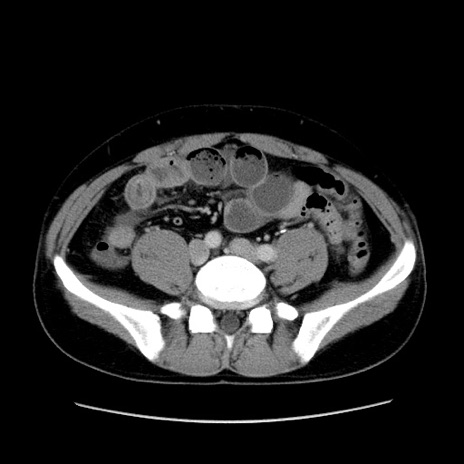

症例4(横断像)

【症例】30歳代男性

【主訴】腹痛、嘔吐

【現病歴】昨晩から突然の腹痛あり、その後嘔吐、軟便も出現。腹痛が改善しないため救急搬送となる。2日前にしめ鯖の食事歴あり。

【身体所見】意識清明、苦悶様、BP 135/90mmHg、BT 35.7℃、腹部:平坦、やや硬、心窩部〜臍部に自発痛、圧痛あり、筋性防御+、反跳痛-

【データ】WBC 8100、CRP 0.57